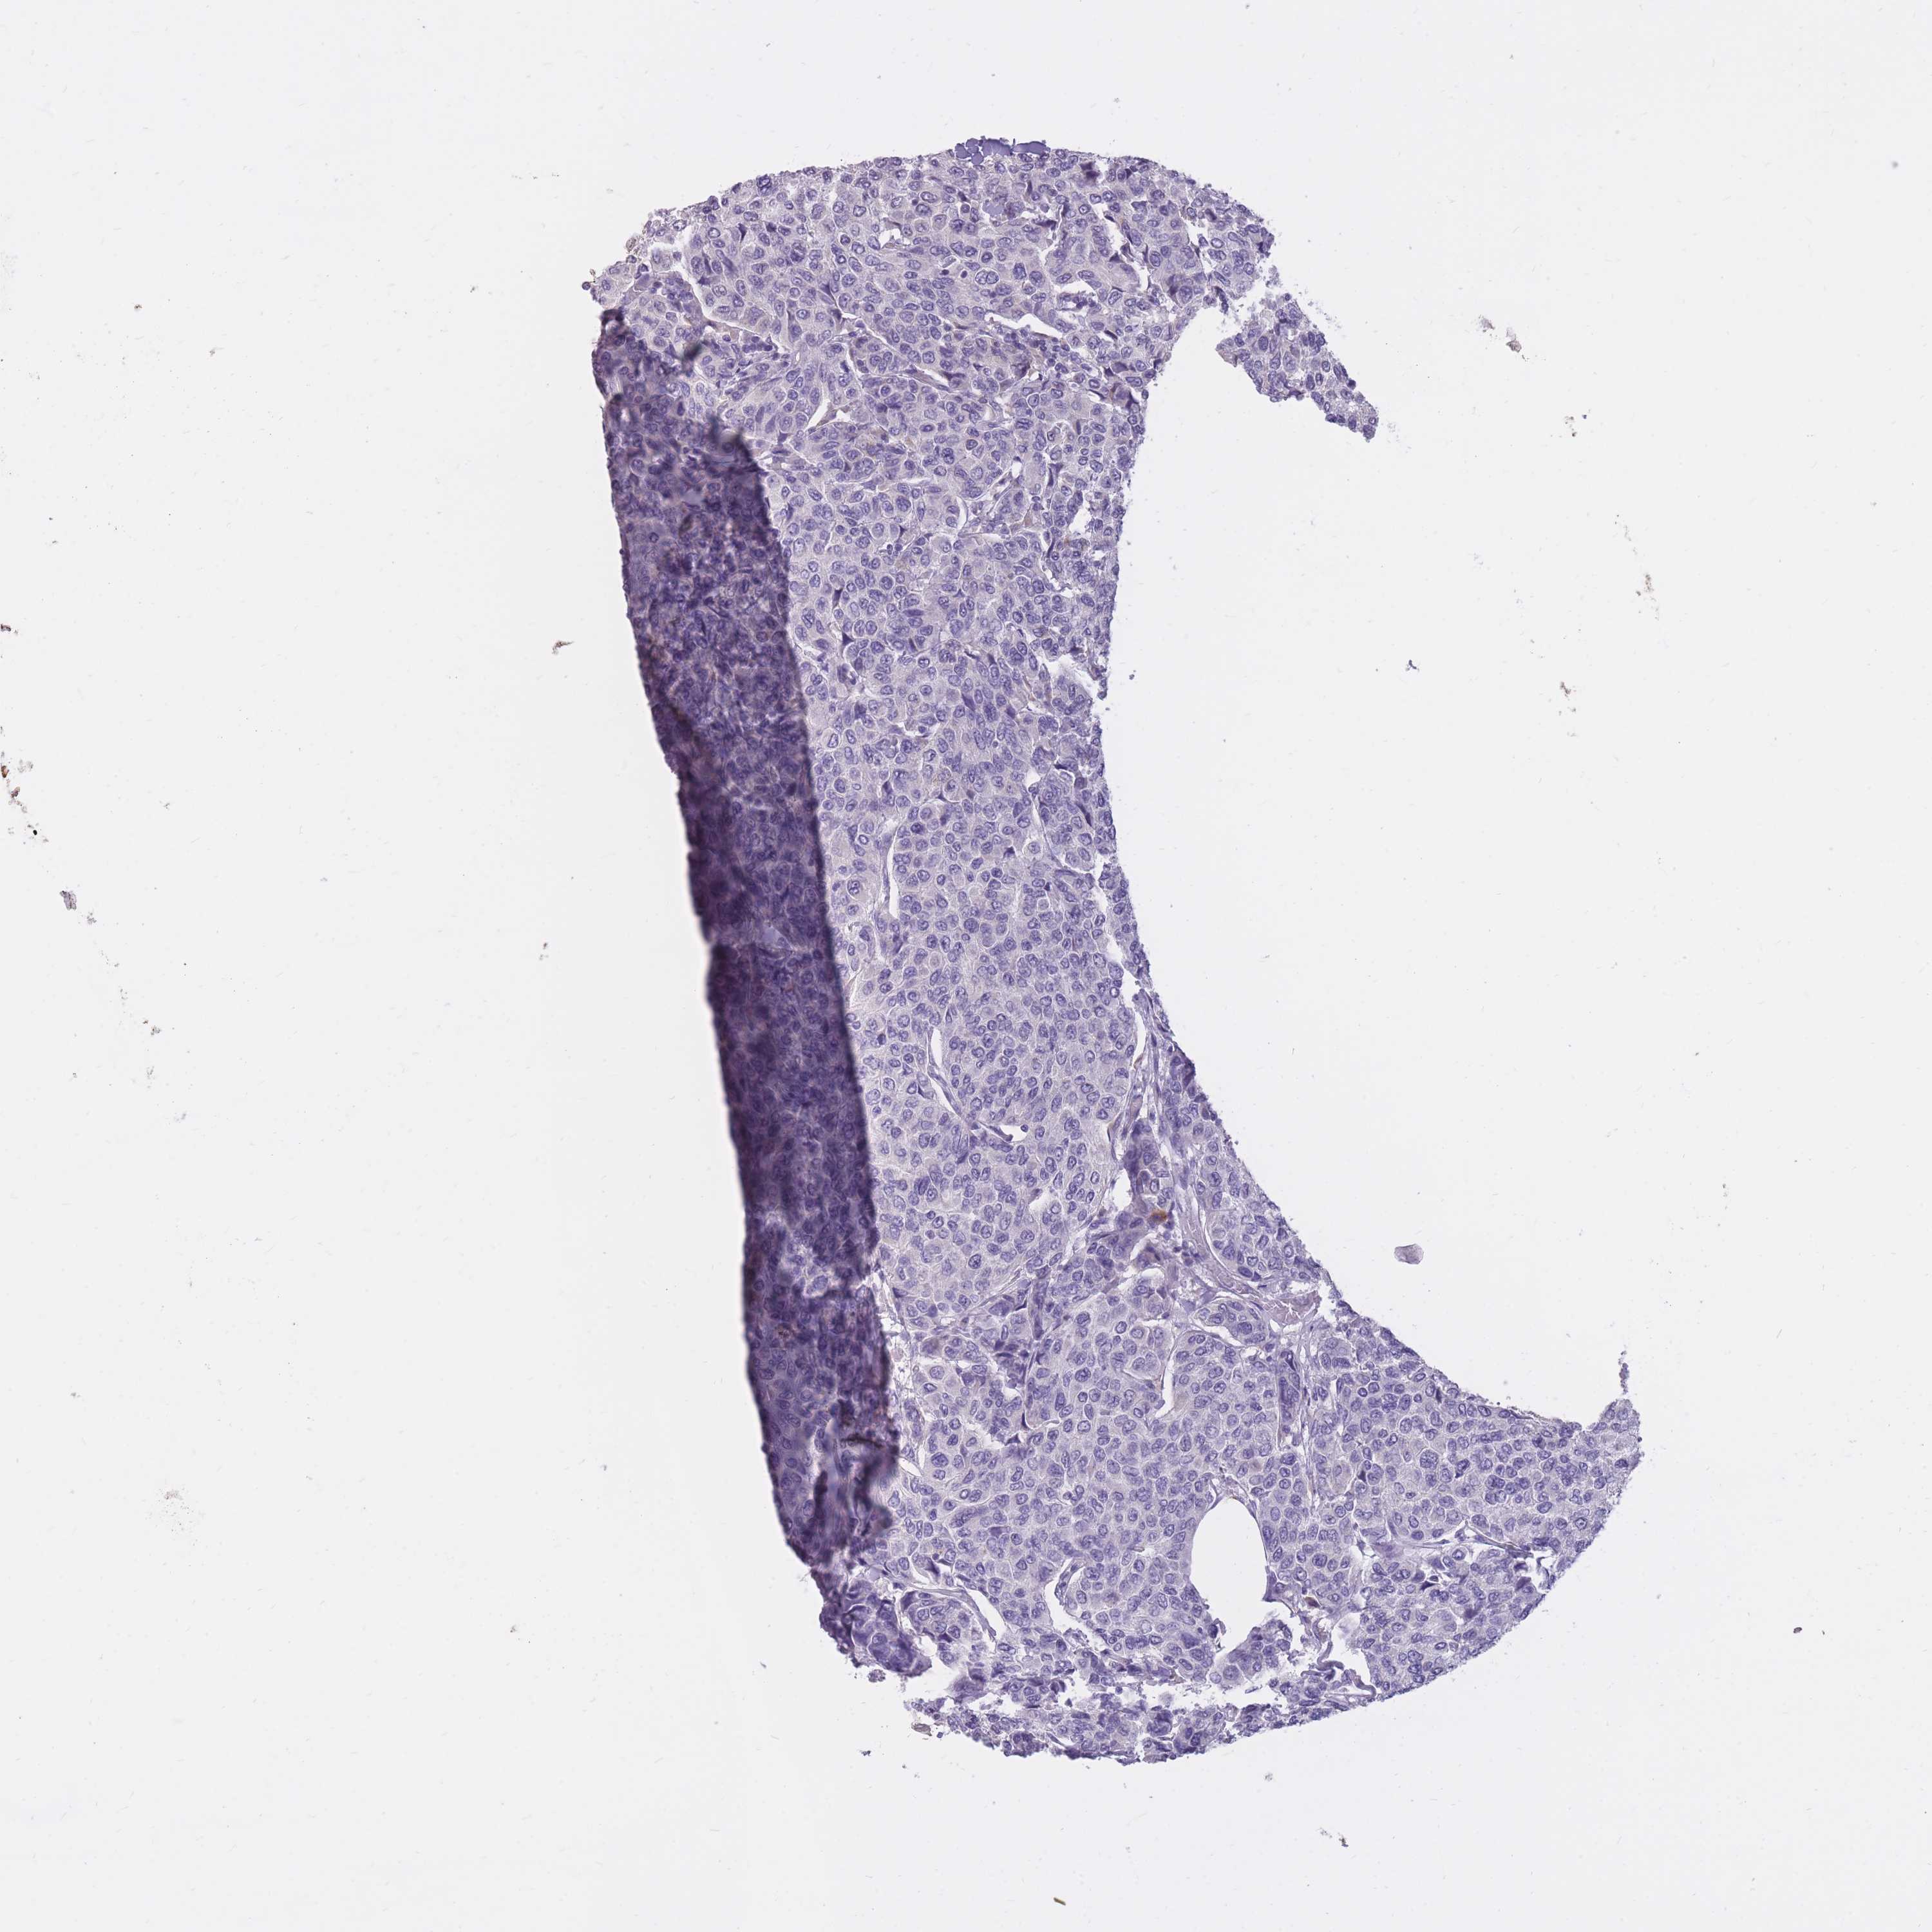

BRCA TCGA BRCA VALIDATION PROTEIN EXPRESSION